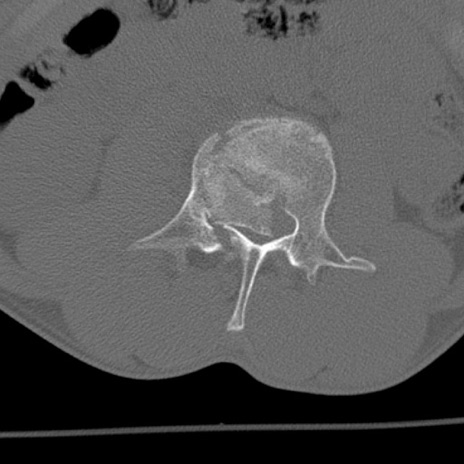

症例3 腰椎CT(横断像)

腰椎CT